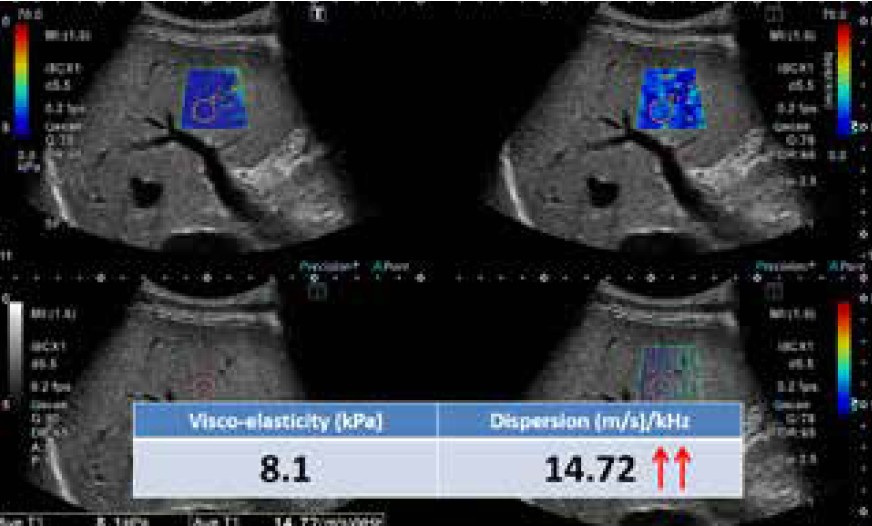

Малюнок 8 Випадок 2: НАСГ

Тромбоцити: 248 × 104 мкл, AСT: 78 ОД/л, AЛT: 172 ОД/л, Загальний білірубін: 0,42 мг/дл

Випадок 1 (Малюнок 7) — це нормальна печінка, а випадок 2 (Малюнок 8) — печінка з НАСГ. НАСГ — це тип стеатозу, який демонструє гістологічні ознаки пошкодження гепатоцитів, включаючи гепатоцелюлярне балонування, часточкове запалення та/або фіброз печінки. Порівняно з нормальною печінкою НАСГ демонструє невелике збільшення еластичності, але залишається в межах норми. Проте спостерігається очевидне збільшення дисперсії.